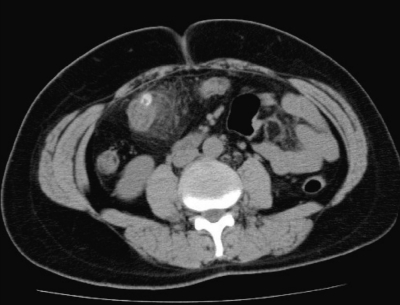

血液所見:赤血球432 万、Hb 13.1 g/dL、Ht 39 %、白血球 15,500(桿状核好中球 32 %、分葉核好中球 58 %、好酸球1%、好塩基球1%、リンパ球8%)、血小板 29 万。血液生化学所見:尿素窒素 10 mg/dL、クレアチニン 0.7 mg/dL。CRP 5.7 mg/dL。腹部超音波検査で肝臓と胆囊とに異常を認めない。腹部 CT の水平断像と冠状断像とを別に示す。

治療として適切なのはどれか。

a. 抗菌薬投与

b. 大腸切除術

c. 虫垂切除術

d. イレウス管による減圧術

e. 体外衝撃波結石破砕術<ESWL>